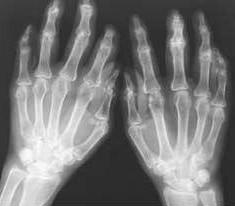

检查: 双手指远端指间关节海伯登结节,关节僵硬,握拳无力。双膝肿胀Ⅲ°,皮温高,浮髌试验(+),屈100°伸-20°,实验室检查:RF(+)(类类风湿因子)血沉65mm/H,C-反应蛋白20mg/L。余指标正常。

(图:李先生初到院时双手X光检查档案)

确诊:类风湿性关节炎